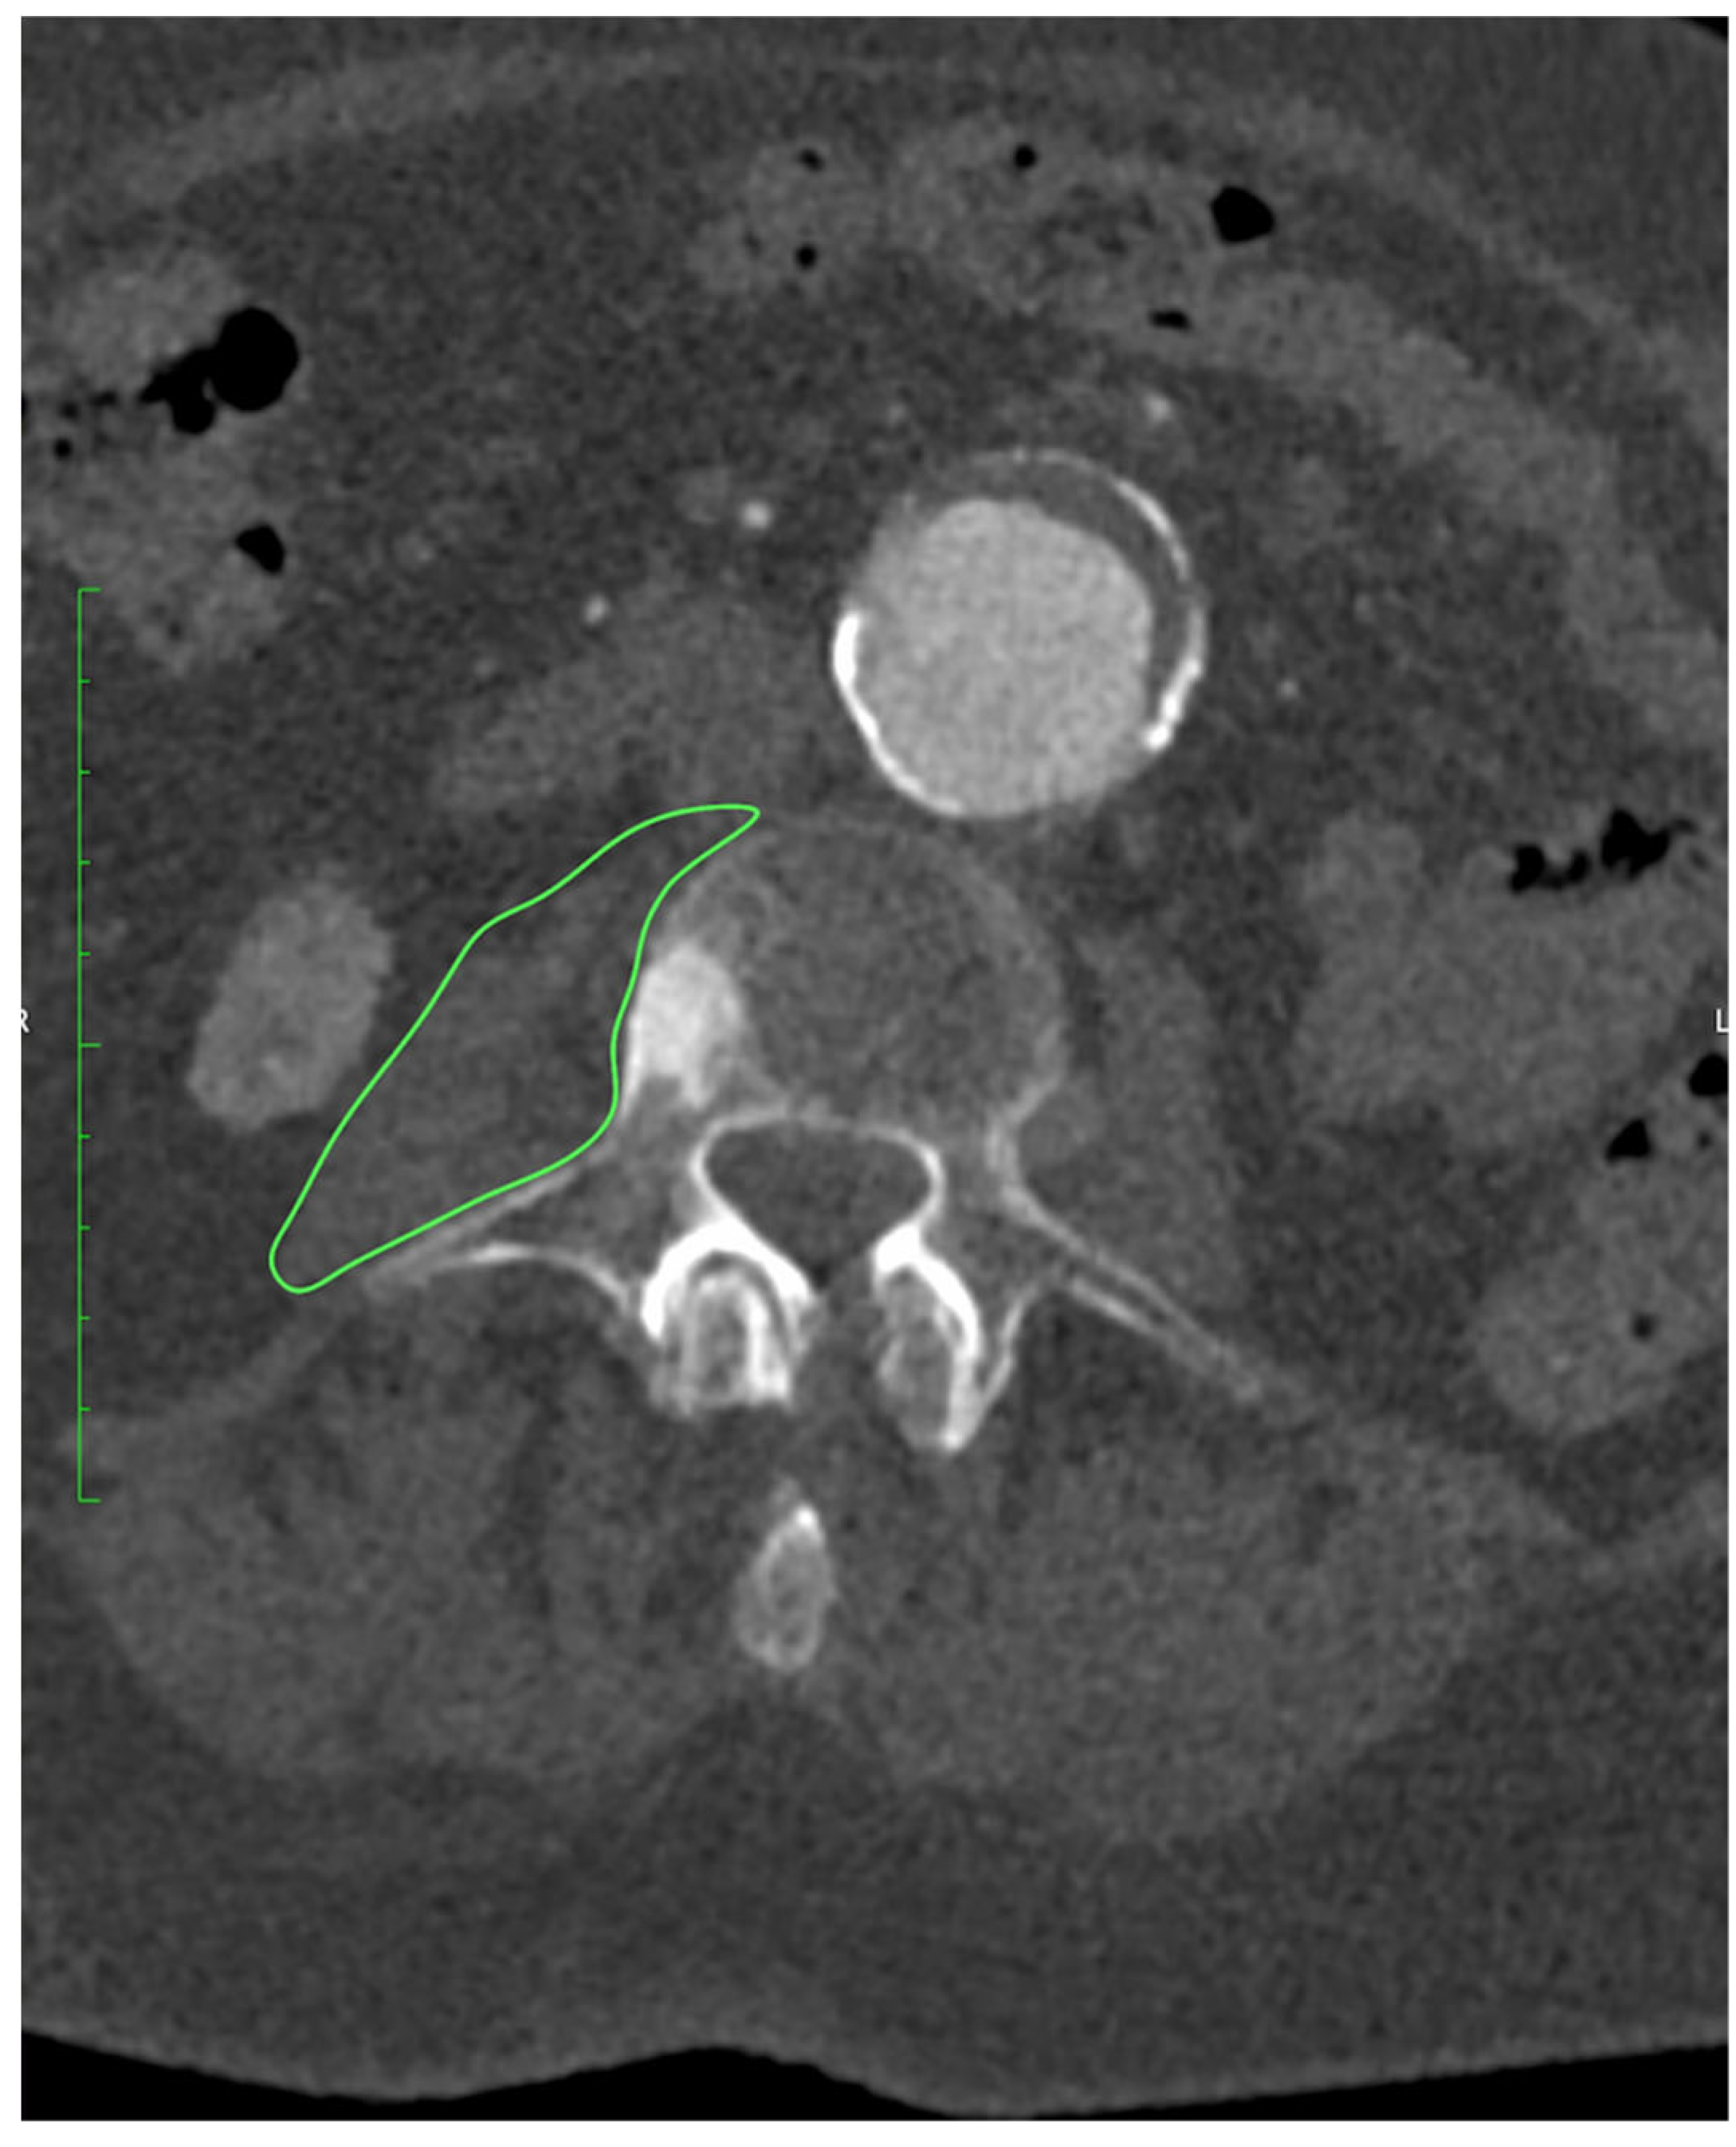

All patients underwent preoperative CTA of the aorto-iliac and femoral arteries performed at our institution. Examinations were acquired on a 128-slice scanner (SOMATOM X.cceed, Siemens Healthineers, Erlangen, Germany) using a standardized contrast-enhanced protocol (100–120 mL of iodinated contrast, injection rate 4–5 mL/s, bolus tracking in the abdominal aorta). Images were reconstructed with a slice thickness of 0.5 or 1.0 mm, depending on the reconstruction protocol used. All scans were obtained on the same scanner model. All measurements were performed preoperatively on CTA at the mid-L3 vertebral level using standardized axial sections in the arterial phase. On a representative slice, both psoas muscles were manually delineated with dedicated imaging software OsiriX MD (Pixmeo SARL, Geneva, Switzerland), version 14.1.0, and their cross-sectional surface areas (PMA, cm2) were recorded, as presented on Figure 1. From the same regions of interest, the average PMD (Hounsfield units) was determined. The PMI (cm2/m2) was derived by normalizing the combined PMA to the patient’s height squared.

Figure 1.

Measurement of PMA at the level of L3 using OsiriX MD (Pixmeo SARL, Geneva, Switzerland), version 14.1.0 software.